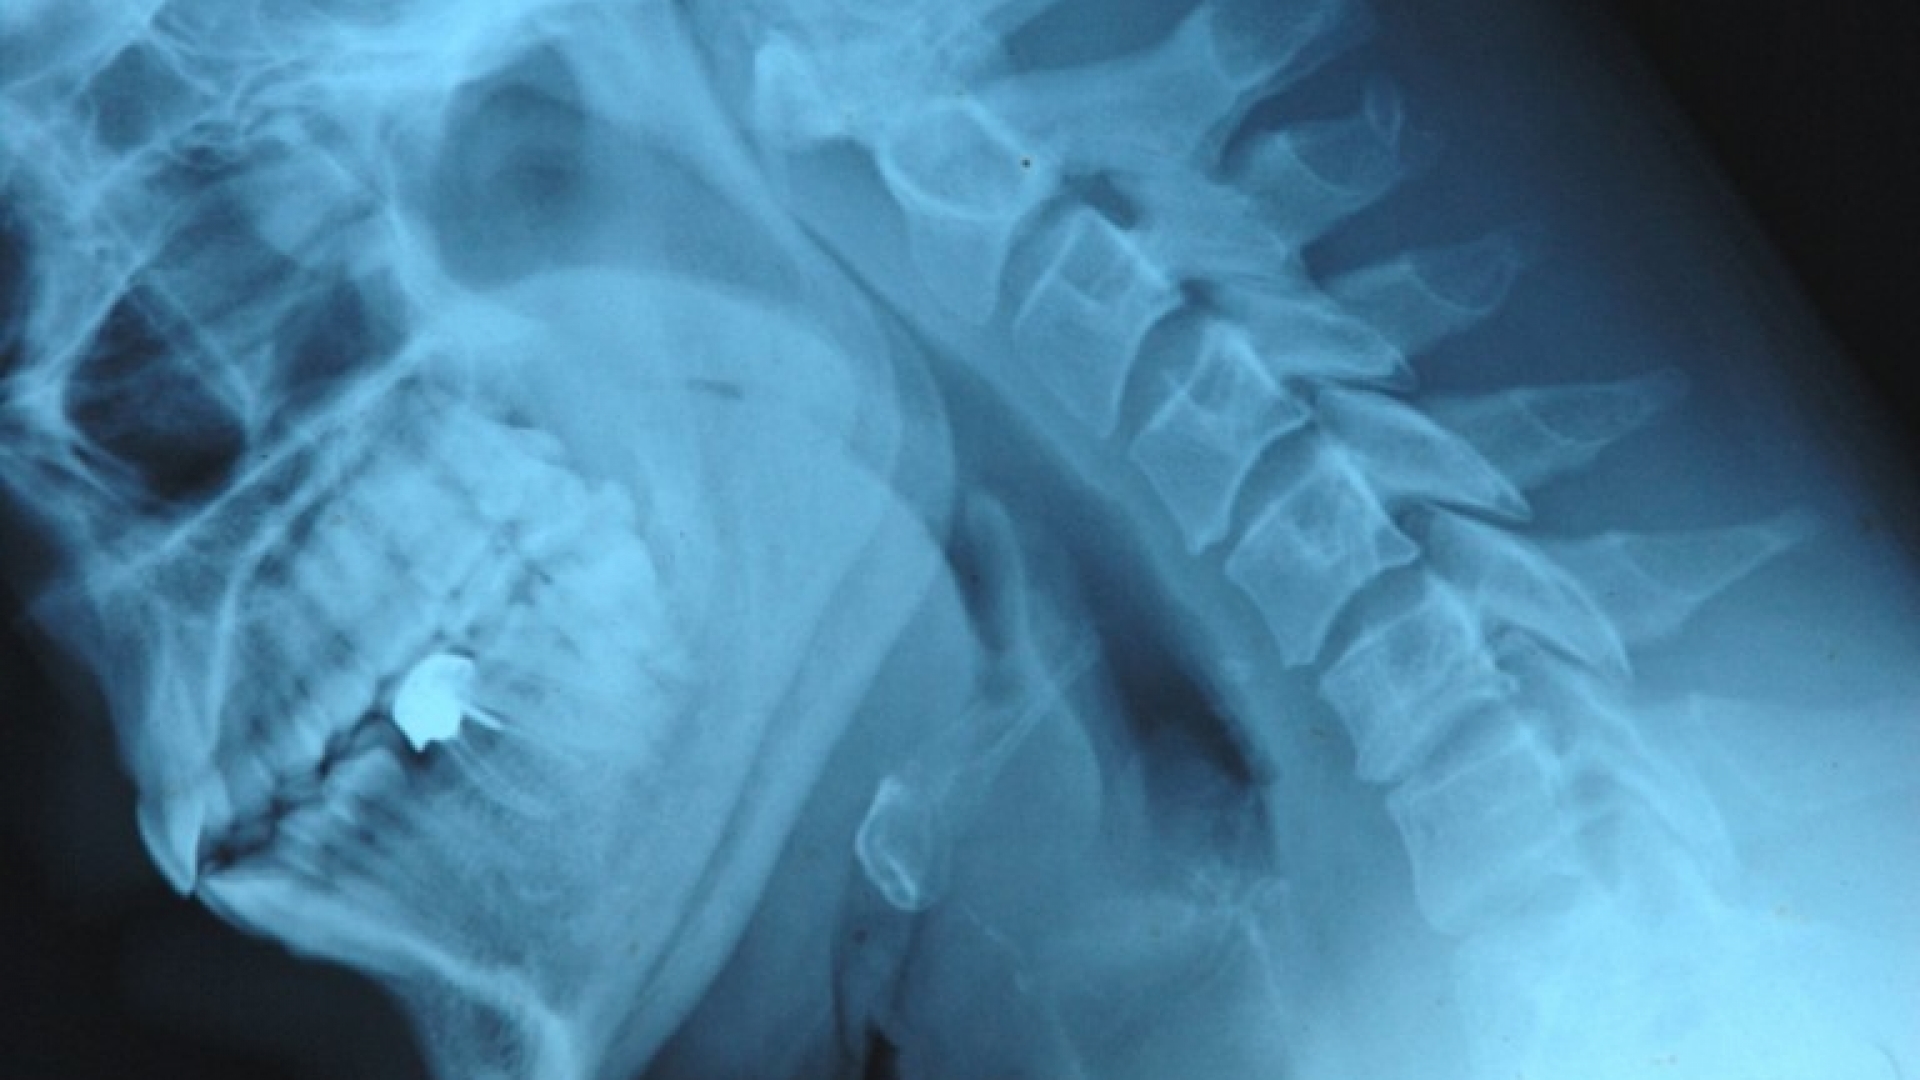

Meistens sehen wir sie nicht. Doch sie sind immer anwesend und beeinflussen unser Leben, unsere Gesundheit, unsere Freizeit. Die Bandbreite der Strahlungsarten ist riesig. Am liebsten ist es uns, wenn uns Sonnenstrahlen wärmen oder uns die Mikrowellen das Essen erhitzen. Trotz der Nebenwirkungen sind wir auch dankbar, dass Röntgenstrahlen schon lange einen Blick in unser Innerstes werfen können. Auf die aggressiven radioaktiven Verwandten würden wir eigentlich gerne verzichten. Und Sie? Wissen Sie, in welchen Bereichen Strahlung noch eine Rolle spielt? Viel Spaß beim Testen wünscht Ihnen die Redaktion!